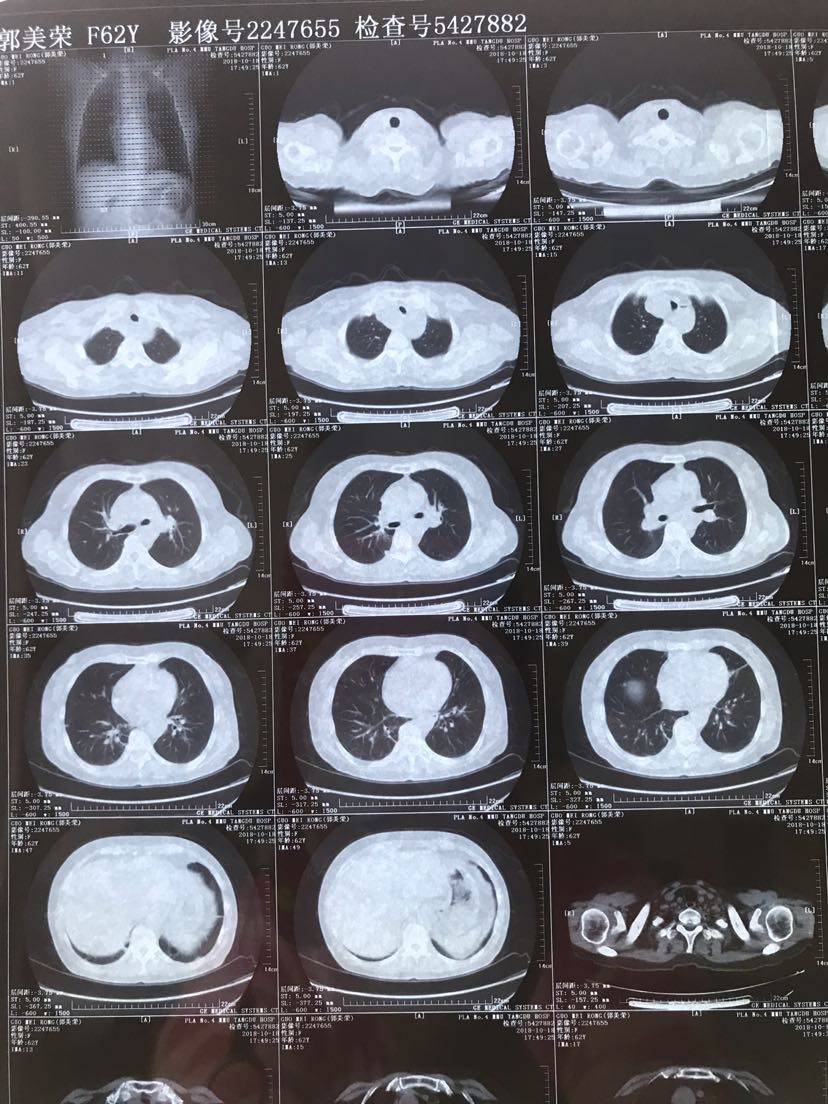

病历.患者,女,62岁,身高163,体重55公斤。2017年5月确诊肺腺癌晚期,胸膜转移,基因检测19突变,服用特罗凯至今。cea不敏感。近3个月体感变差,胸部牵扯痛,深呼吸痛,ca199从个位数升到74。周五复查发现进展了,如下图。

以下是8月的CT(1)